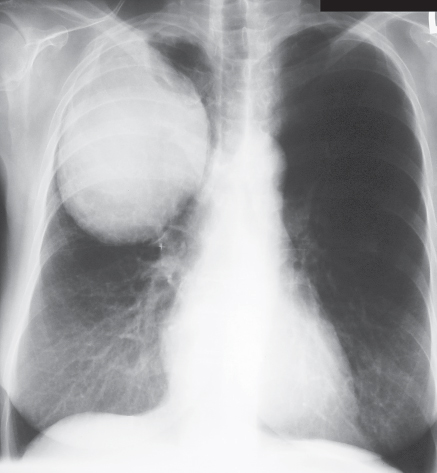

Pleural Effusion

Feature Description

Blunted costophrenic angle Loss of sharp angle between diaphragm and chest wall.

Fluid layering Horizontal fluid level, more evident on erect or decubitus views.

Meniscus sign Crescent-shaped opacity rising higher laterally than medially at the lung base.

Left-sided pleural effusion

Chest X-ray with a left-sided pleural effusion